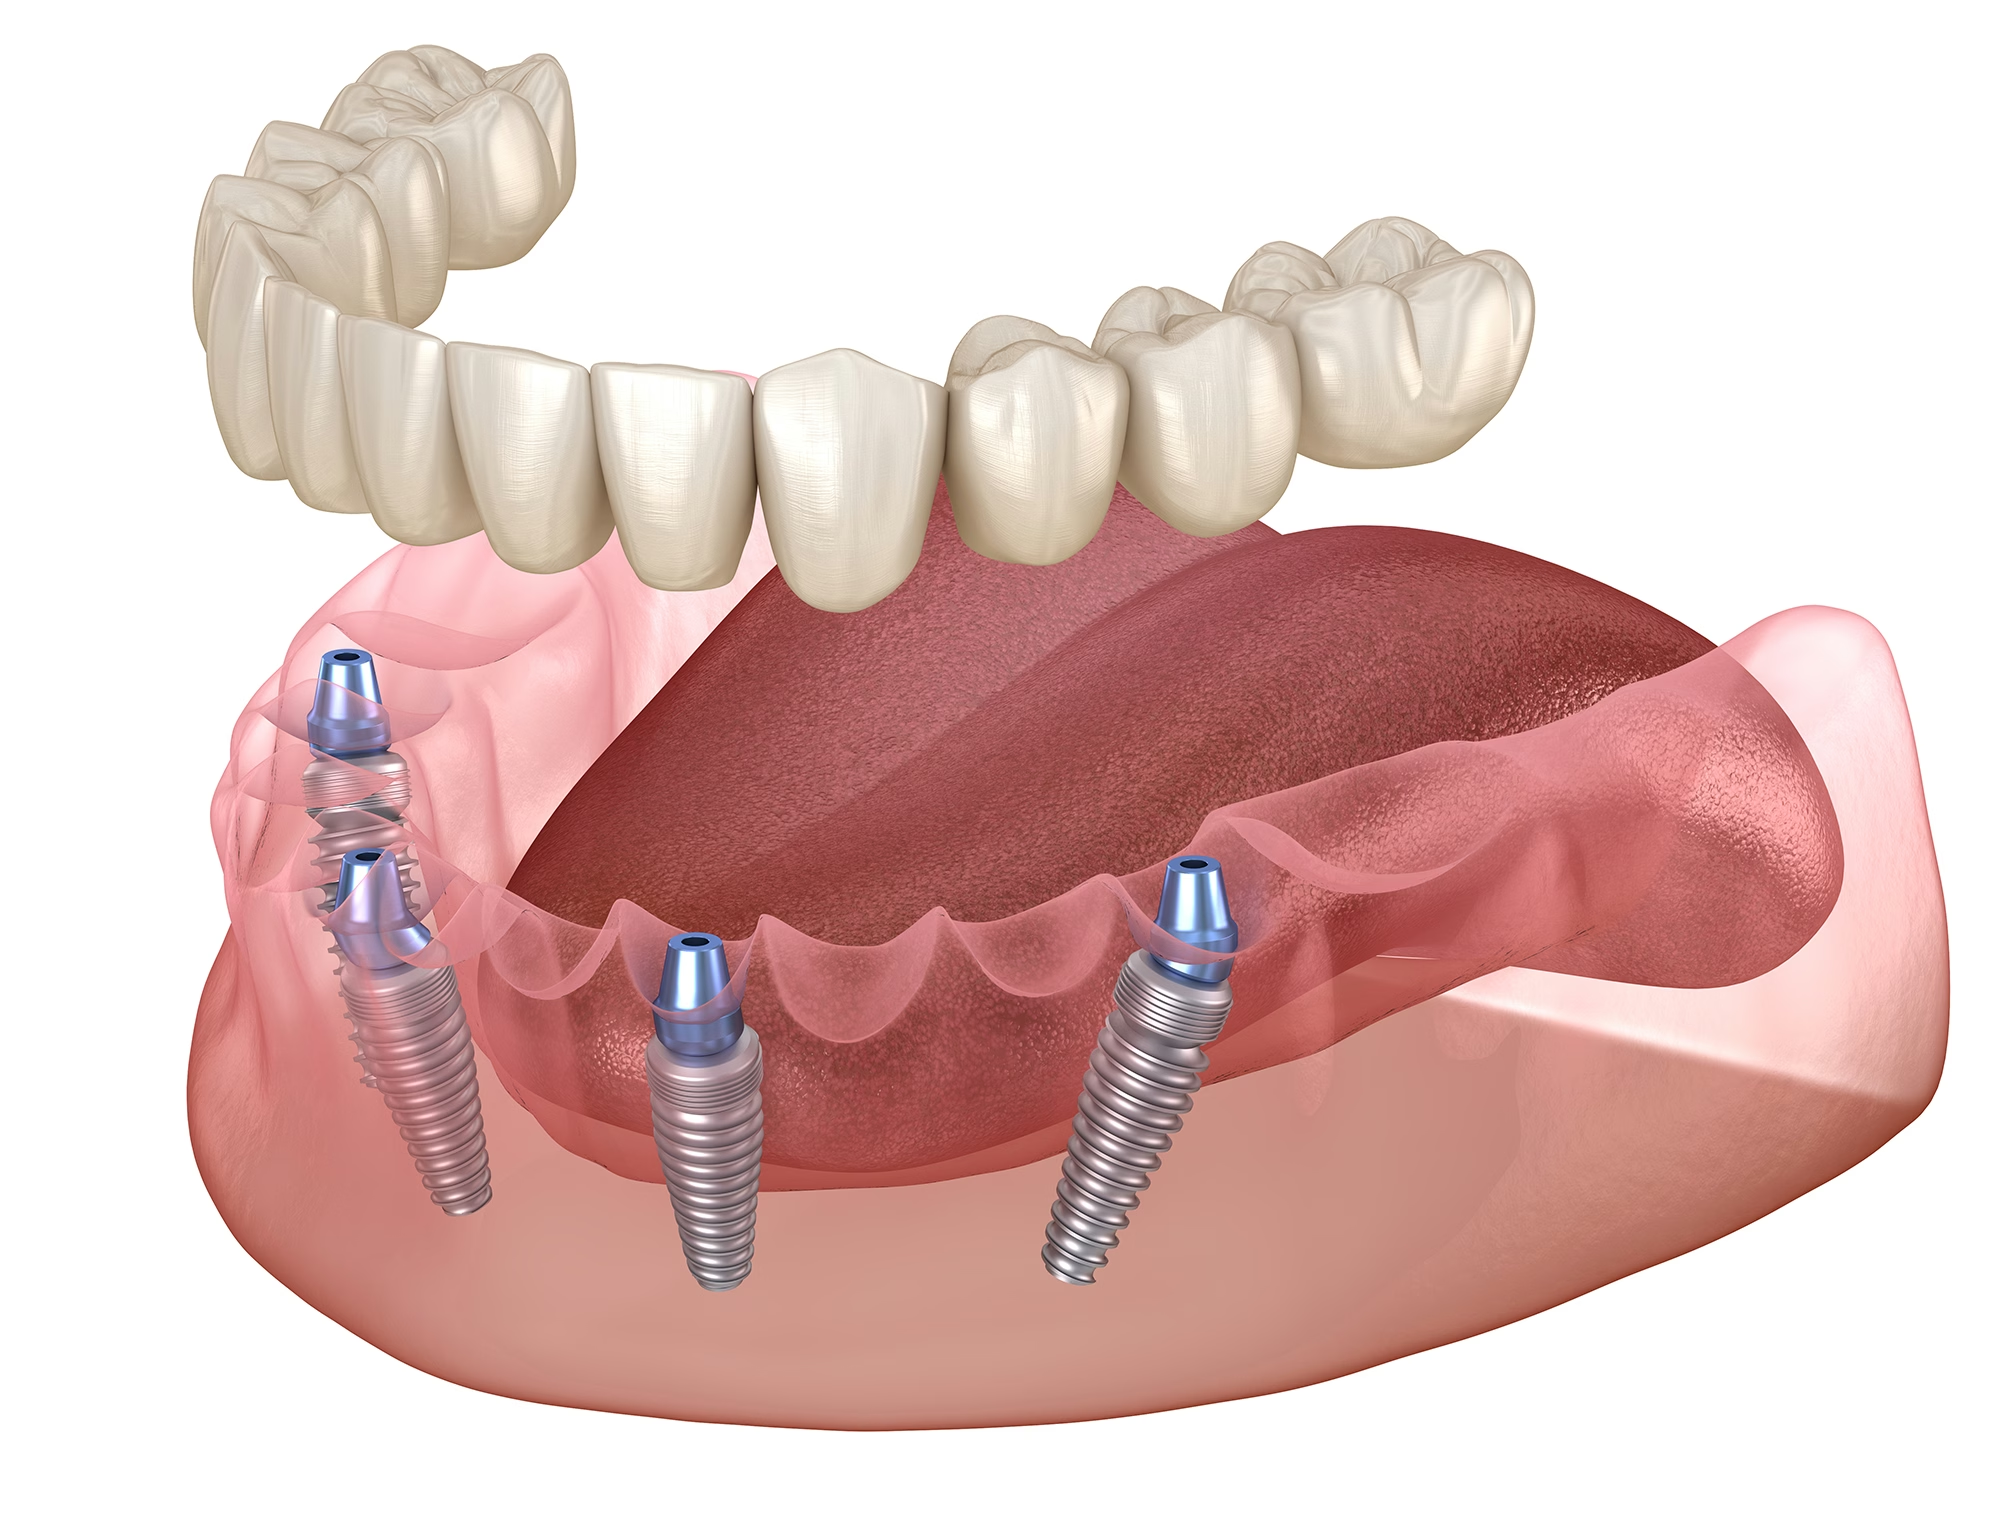

1. Bridges sur Pilotis et All-on-4 / All-on-6

La solution fixe de référence pour une réhabilitation complète. Que l'armature soit réalisée en Titane ou Chrome-Cobalt, elle est transvissée sur vos implants pour une stabilité inébranlable. Finition esthétique avec fausse gencive résine ou composite pour gérer les pertes de volume osseux.

2. Barres Implantaires pour Prothèses Amovibles

Galerie de cas en Implantologie

Apercu de cas implantaires sur mise en charge immédiate. Entre la prise d empreinte et la pause chirurgicale.